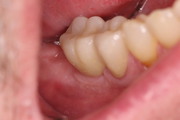

Socket + Implantation 3,5 Jahre Follow up

Nach Entfernung der Zähne 46 und 47, Augmentation DentOss fein, Adaptationsnähte, 6 Tage danach, Implantation nach 5 Monaten und ZE 45, 46 mit Zirkonkronen.Röntgenkontrolle nach einem Jahr und klinische Situation. 3,5 Jahre nach Socket.